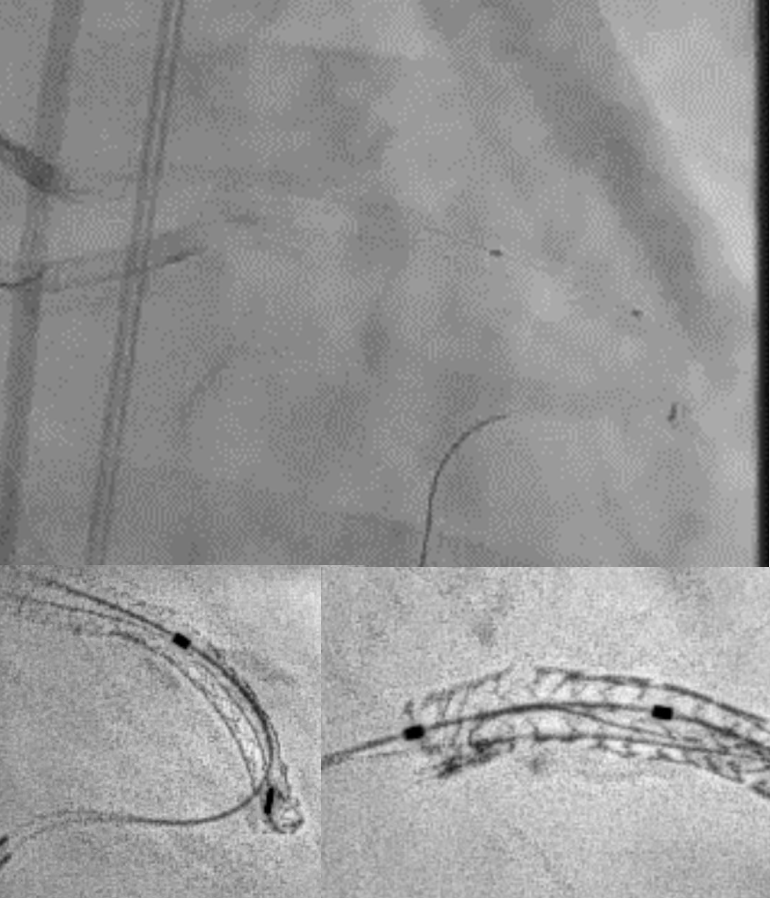

Upon removal of the workhorse wire from distal LAD, an unforeseen nightmare started. The wire tip entangled with the distal stent edge. Turnpike microcatheter was used to retrieve the stuck wire. Unfortunately, upon pullback, the wire fractured and only its proximal part was retrieved. The distal part remain stuck in the distal stent edge and uncoiled with filaments extending from stent edge into aorta. PingPong guiding was immediately set up. ClearStent showed distal stent edge deformity which rendered passage of any device including 1.0mm balloon impossible. In order to modify the obstructing stent struts at distal edge, it was decided to use rotablation. Direct wiring across the deformed distal stent edge with rota wire was successful. Pecking motion of rotablation was performed with the aim to clear the obstructing scaffolds. After 25 runs at high speed with 1.5bur, the deformed distal stent was successfully crossed. The trapped wire tip was unexpectedly released and fell into the septal branch. The fractured filaments were assessed with IVUS and ClearStent. Subsequently, the filaments were all retrieved with 2 twisting wires. IVUS confirmed complete clearance of any filament. The LM-LAD stent was again post dilated and optimized. Final angiogram and follow up restudy 4months later both showed satisfactory result with patent stents.

In this case, combined use of rotablation atherectomy and twisting wires successfully salvaged a nightmare and saved the patient from extremely high risk open heart surgery. Staying calm, using essential PCI techniques, different devices and imaging are the keys in tackling potential life threatening complications.